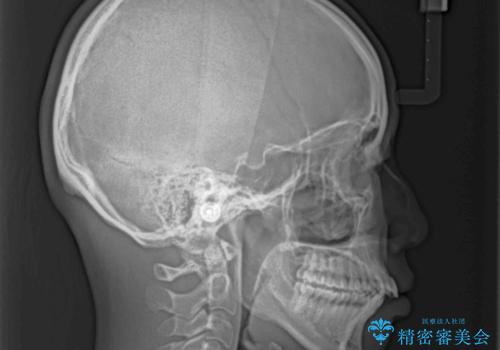

- 前歯の出っ歯と口元の閉じにくさを気にして来院された患者様です。

口元を積極的に引っ込めるために、上下左右の小臼歯4本を抜歯し、目立たないワイヤー装置にて矯正治療を行うこととしました。

上下前歯の歯軸の角度が大きく改善され、お口を閉じたときに顎先に認められた梅干し様の皺も改善されました。